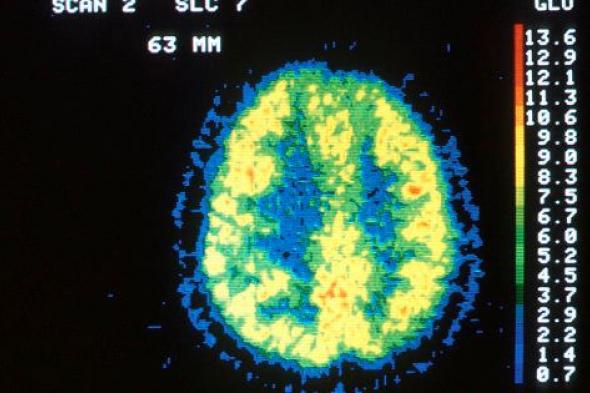

¿Qué ocurre en el cerebro durante la meditación?